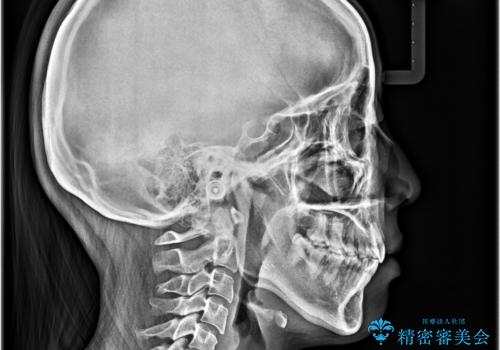

- 口元から飛び出てしまう前歯を気にして来院された患者様です。

上下前歯が嘴のように前方に突出しており、唇が閉じにくい状態であったため、上下左右の第一小臼歯4本を抜歯して、口元の突出感を改善することとしました。

口元の印象が劇的に解消され、気にしていたガミースマイルも図らずも改善することができました。